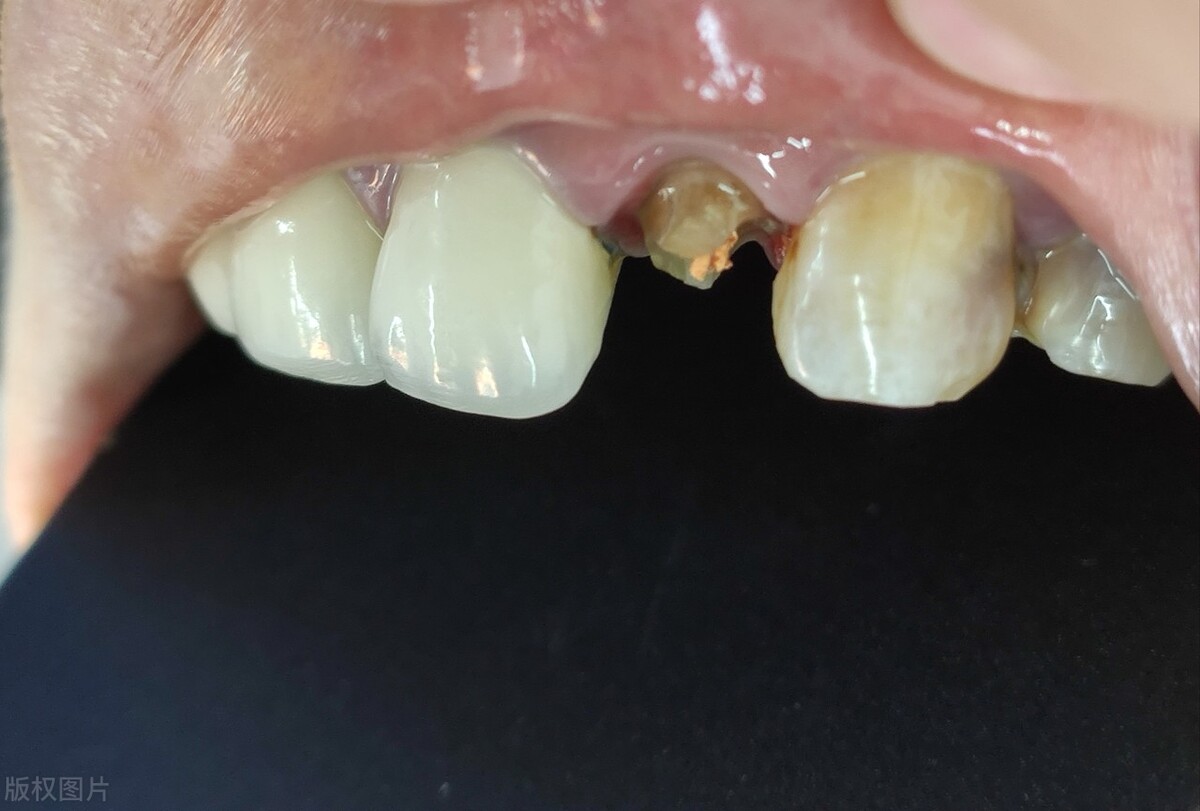

2、残根牙

残根牙,一般是龋坏拖延不治,导致牙齿烂得只剩下一个牙根。这时,牙医也会建议尽快拔除,因为残根相当于一个带有龋坏病菌口腔病灶,不仅牙齿没有实用功能,残根锐利的边缘还会刺激牙龈,引起口腔溃疡,严重的甚至会诱发牙龈瘤。

残根牙